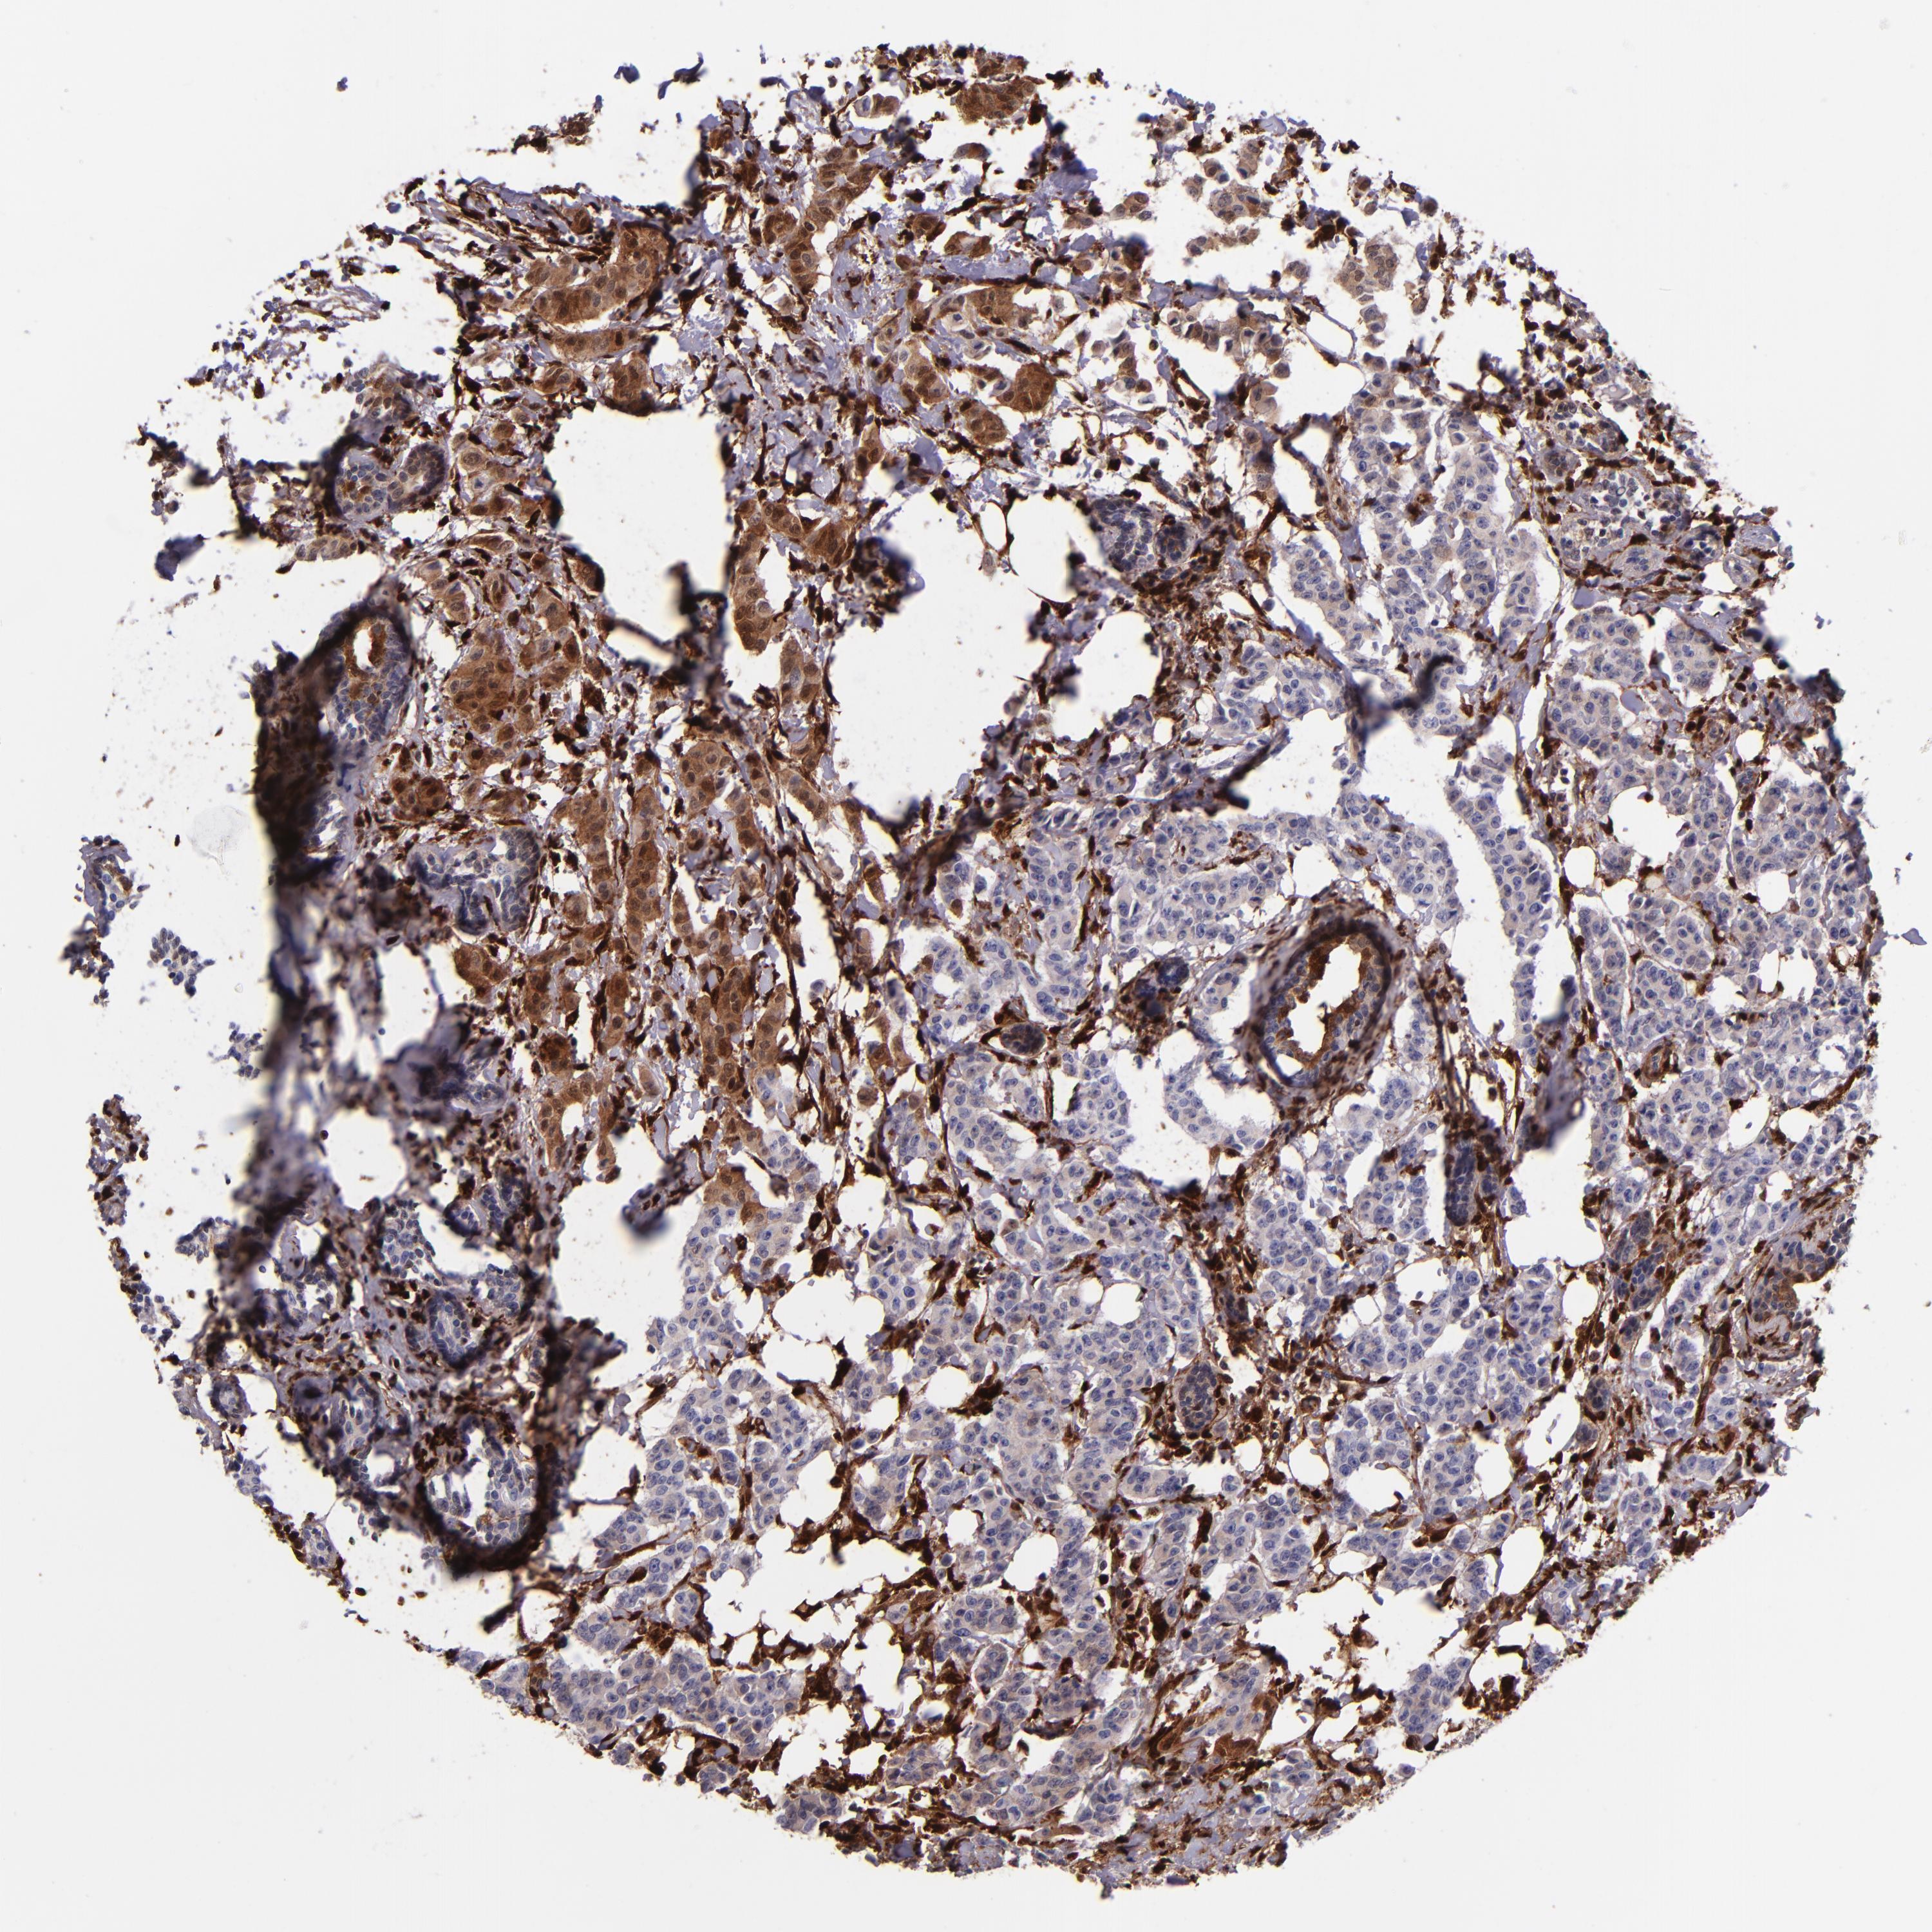

CANCER BREAST CANCER Show tissue menu

BRCA TCGA BRCA VALIDATION PROTEIN EXPRESSION